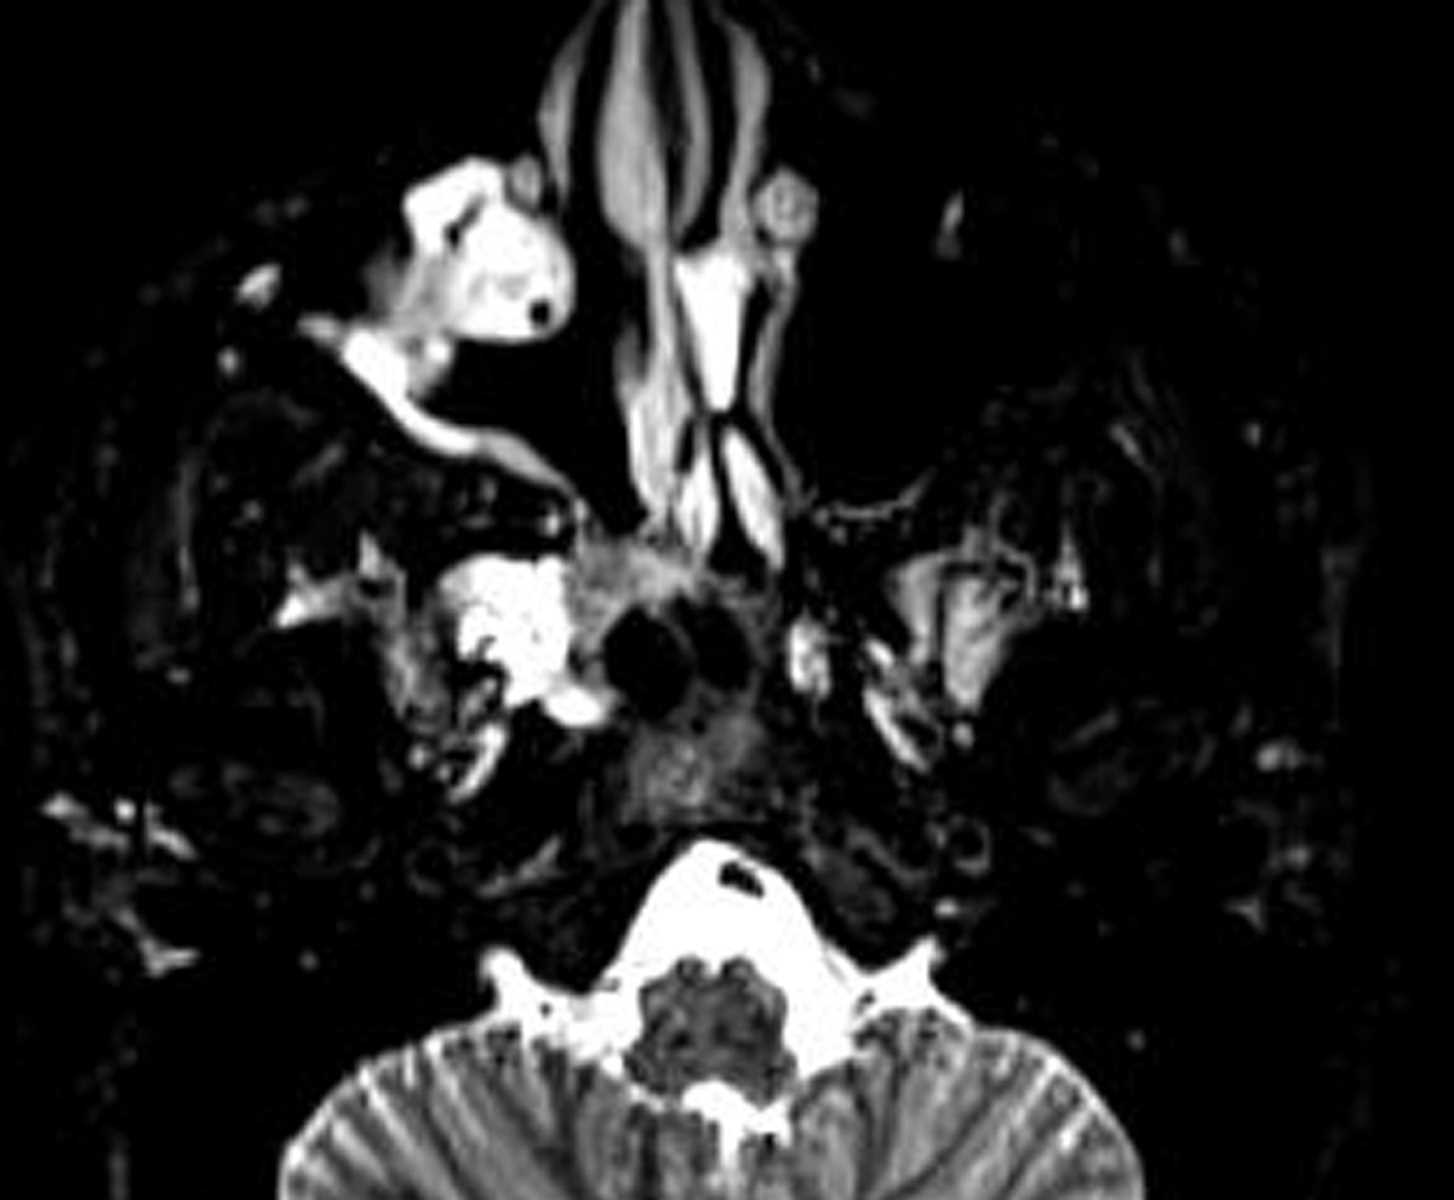

Meningioma (Planum Sphenoidale)

A large enhancing extra-axial mass is demonstrated along the planum sphenoidale, additionally insinuating into the olfactory groove, consistent with a meningioma. Mass effect on the frontal lobes, optic nerves, optic chiasm, and pituitary infidibulum was present. No cavernous sinus invasion or vascular occlusion was seen.